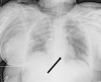

Paciente de 24 años que ingresa tras politraumatismo por accidente de tráfico. En radiografía de tórax inicial se objetiva intubación selectiva de bronquio derecho. Tras recolocación, presenta de tubo orotraqueal inestabilidad hemodinámica y desaturación con relación a neumotórax bilateral a tensión, por lo que se realiza toracocentesis bilateral, con mejoría de oxigenación pero persistencia de inestabilidad hemodinámica. En Rx de control (fig. 1) se visualiza neumomediastino y neumopericardio que se confirma por TAC torácico, procediendo a la colocación de drenaje pericárdico (fig. 2), con mejoría global. En la TAC se diagnostica rotura traqueal distal que se maneja con aislamiento de la misma mediante recolocación de tubo orotraqueal guiado con fibrobroncoscopia con resolución del cuadro en los siguientes días.